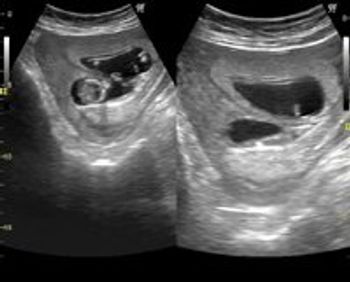

Our patient presented at 29 weeks gestation for a routine prenatal ultrasound.

There are multiple anomalies in these ultrasound images of a second trimester pregnancy.